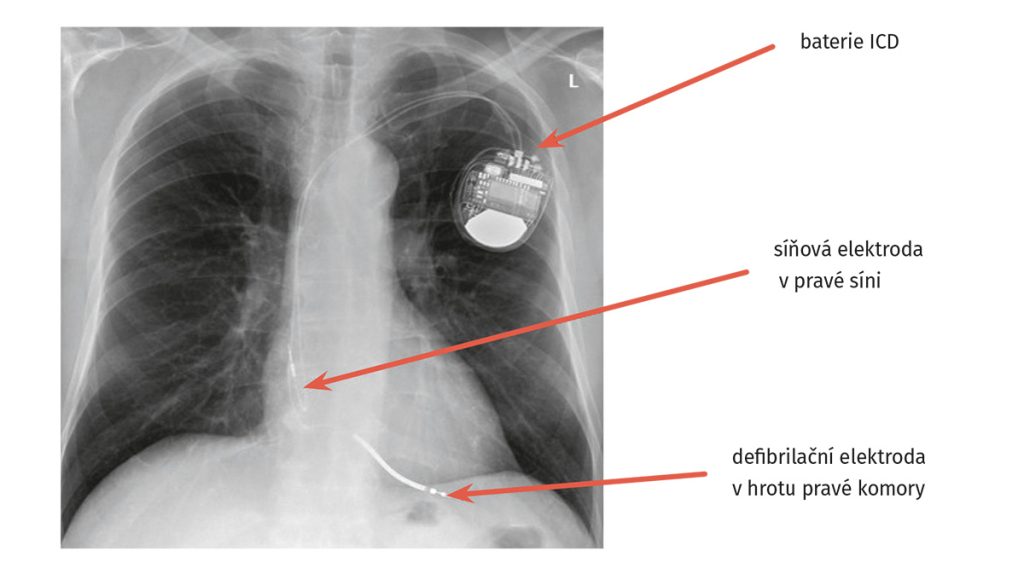

Byla doplněna nukleární magnetická rezonance srdce prokazující netransmurální ischemické ložisko v oblasti spodní a boční stěny levé komory se snížením ejekční frakce levé komory < 40 %. Vzhledem k těžké dysfunkci levé komory byla u pacienta provedena implantace defibrilátoru (ICD) v primární prevenci náhlé srdeční smrti (obr. 1 a obr. 2).

Obr. 1 Rtg hrudníku po implantaci defibrilátoru